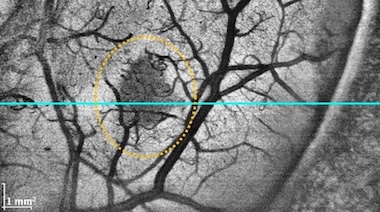

"We see our microscope-integrated MHz-OCT system being used not just in brain tumor surgeries, but as a tool in every neurosurgery setting, since it can acquire high contrast pictures of anatomy such as blood vessels through the thick membrane that surrounds the brain," said Draxinger.